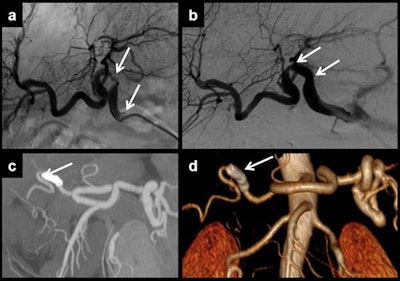

The most frequently affected anastomosis is at the hepatic artery, they continued. This anastomosis can be made in different places, but the two most frequent are in the hair-pin space between the right and left hepatic arteries of the recipient or at the outlet of the gastroduodenal artery.

In the first three days after liver transplantation, an increased resistance index of the hepatic artery (greater than 0.8) is found in approximately 50% of the patients, they pointed out. If found, it should be monitored until it has normalized, typically on the fourth day after transplantation. Although the severity of the described findings correlates with the degree of the stenosis, ultrasound does not allow proper quantification of this, and the technique of choice is CT angiography. In addition, CT allows proper evaluation of patients with a poor sonographic window while MR angiography is a limited technique because of a relatively high false-positive rate, they added.

"Hepatic artery stenosis requires early treatment. First, an angiography and an angioplasty should be made. If this procedure fails, surgery is required. Once again, retransplantation has a better outcome, but is preferred as a second-line treatment to use when endovascular therapy does not work," they concluded.